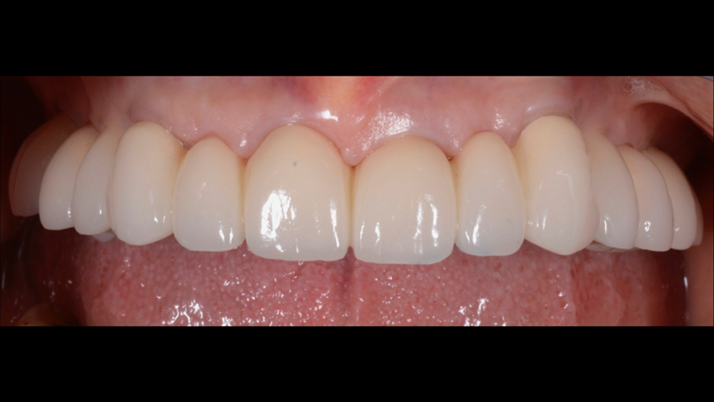

“AnyRidge shows excellent esthetic results

with Zirconia prosthesis in full-mouth rehabilitation case . ”

Clinical case: A Full transition from natural teeth to all-on-6 bridges

with AnyRidge implants

- Courtesy of Dr. Rabih Abi Nader, UAE -